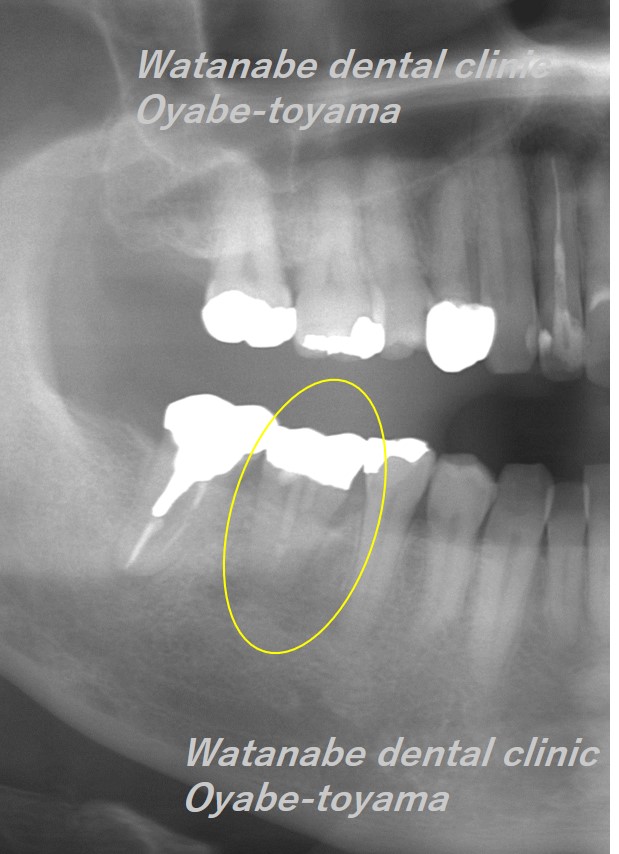

移植後2年経過しました。

移植した歯の周囲には歯槽骨の再生も確認でき、良好に経過しています。